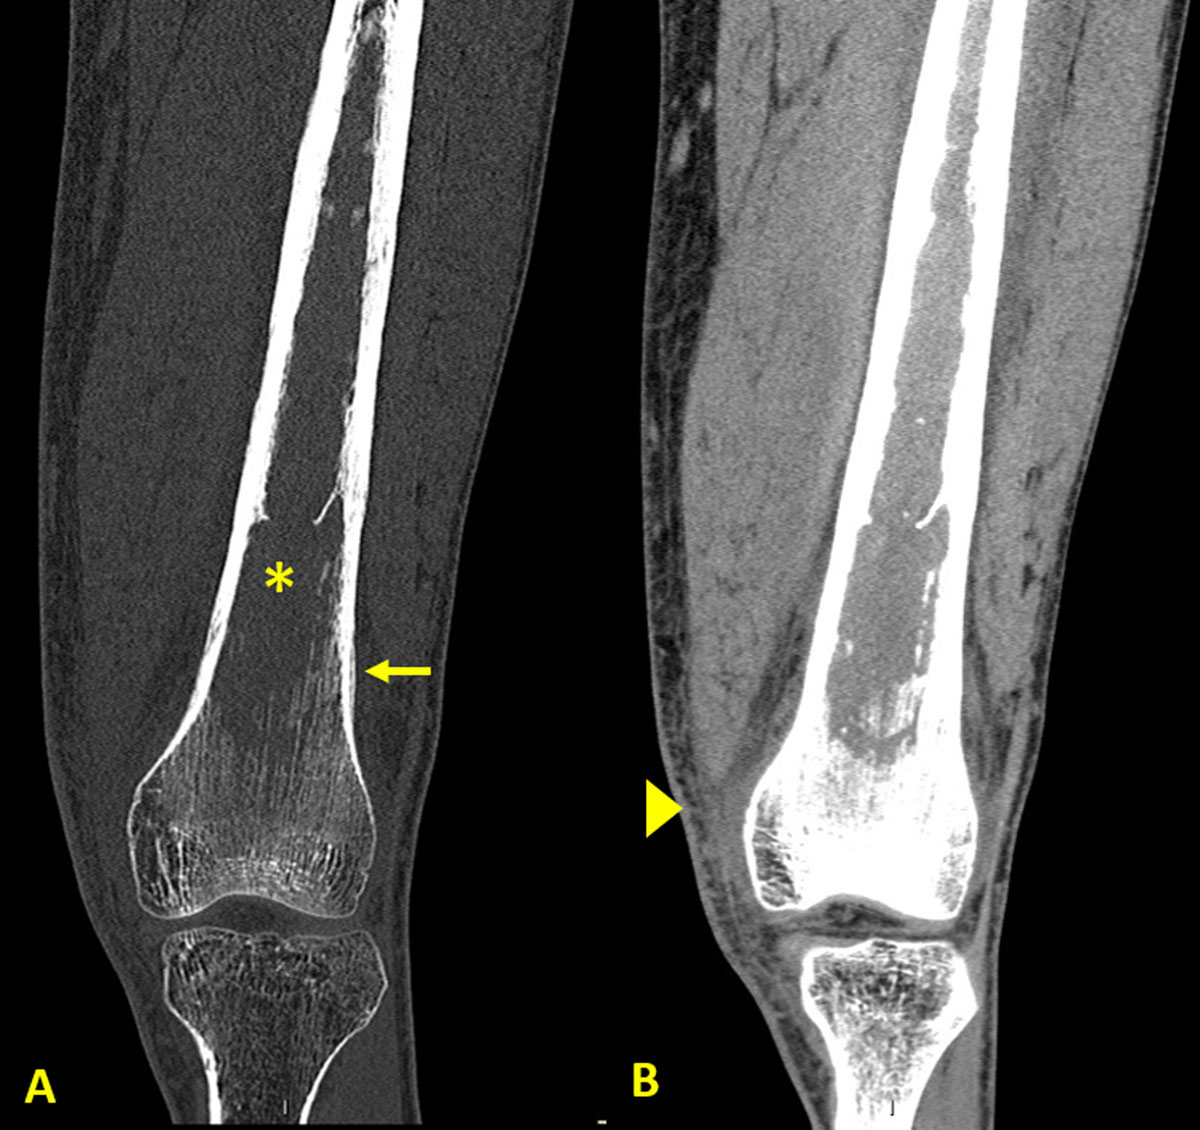

Figure 2

CT of the knee showing preserved integrity of the femur’s cortex.